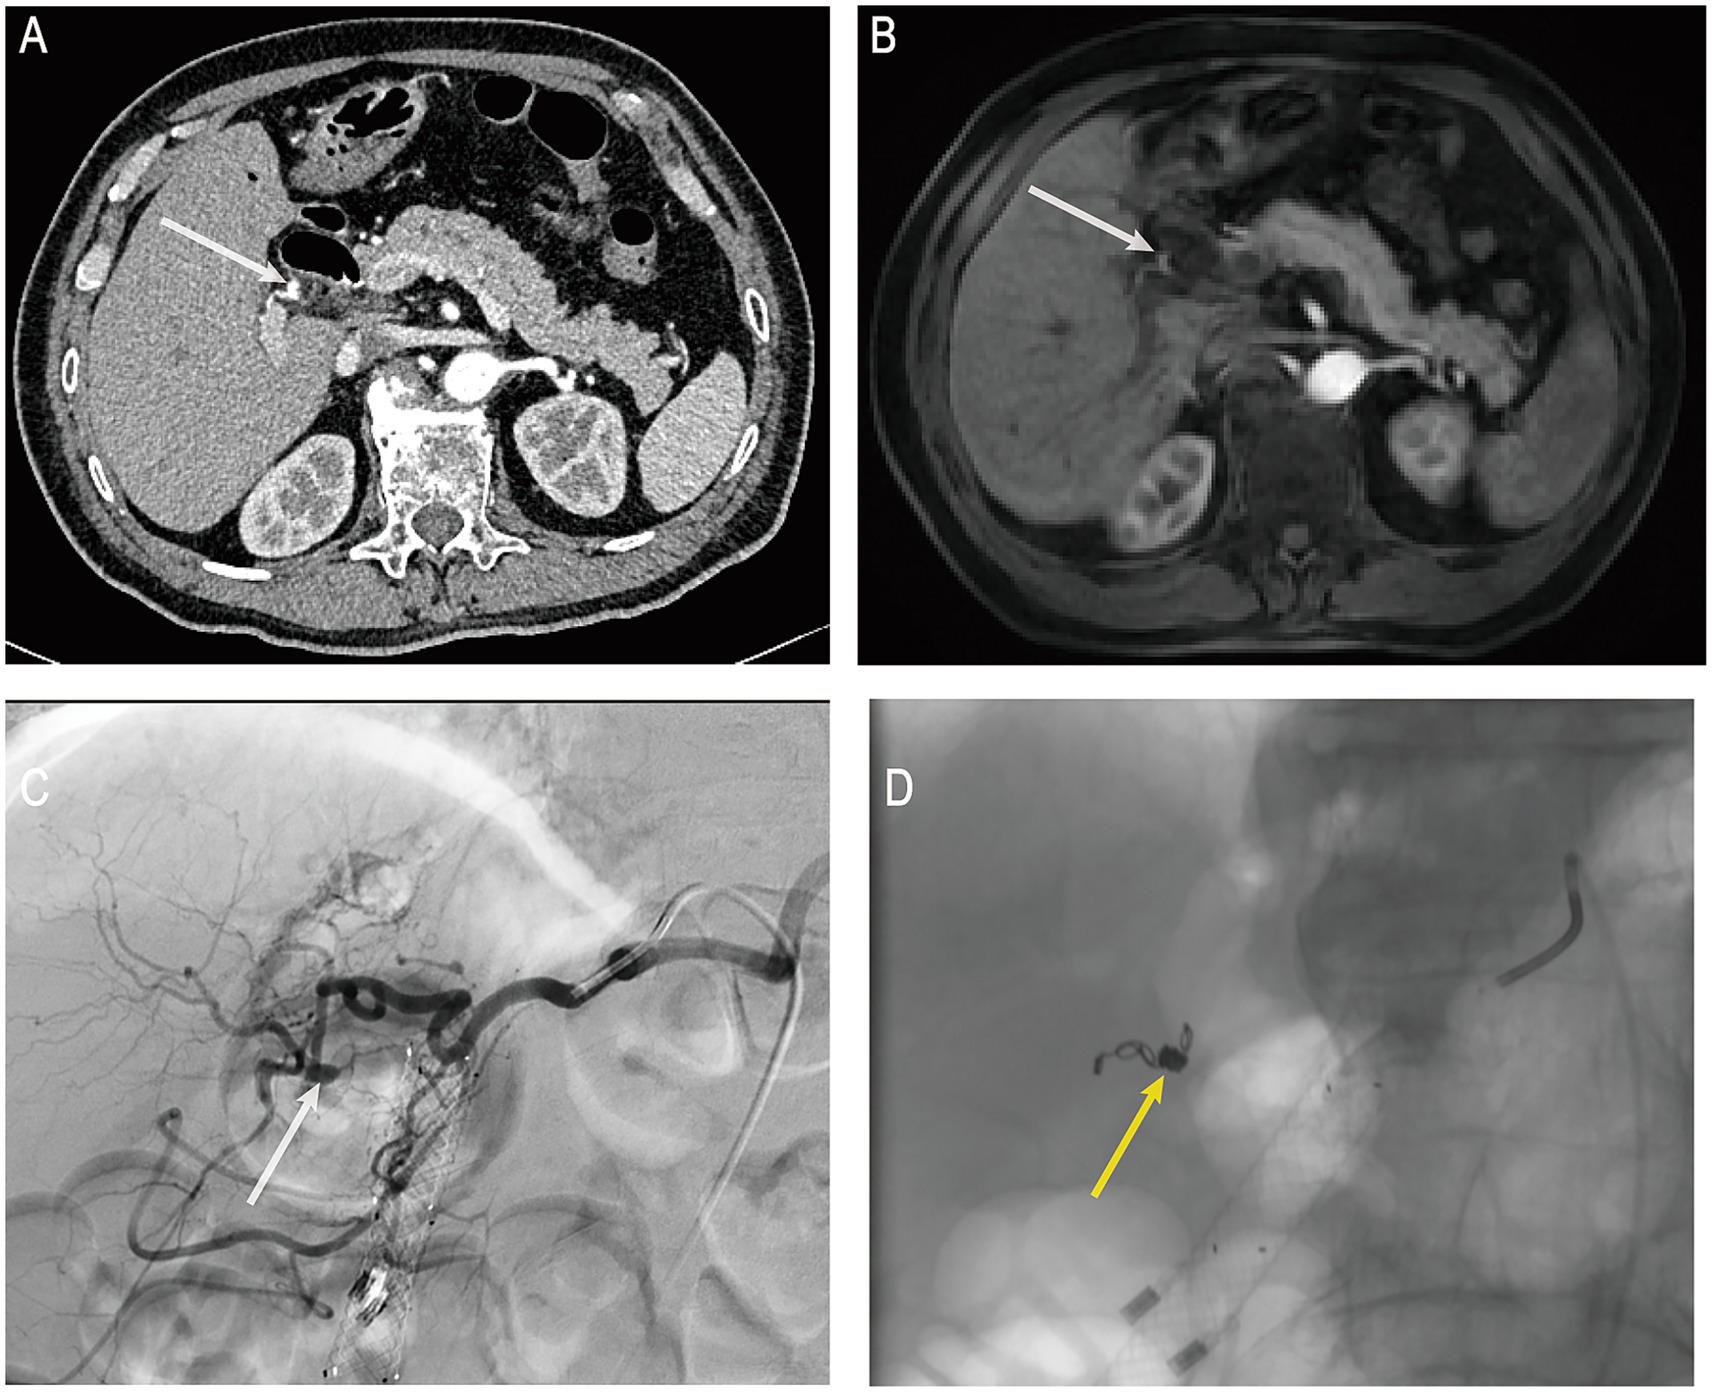

On the day of the procedure, the patient’s blood pressure dropped to 84/53 mmHg, accompanied by altered consciousness, clammy skin, and other signs of hemorrhagic shock. Hb further declined to 73 g/L, indicating ongoing active biliary bleeding. Emergency computed tomography angiography (CTA) revealed a mildly dilated, nodular change in the proximal right hepatic artery measuring approximately 4 × 4 mm (Figure 3A), suggestive of an aneurysm or HAP. No aneurysm had been identified on pre-ERCP MRCP imaging (Figure 3B), supporting the likelihood that the lesion developed secondary to ERCP-related procedural trauma. Following a multidisciplinary consultation, emergency digital subtraction angiography (DSA)–guided hepatic artery angiography and transcatheter arterial embolization (TAE) were performed under local anesthesia. DSA demonstrated a pseudoaneurysmal outpouching of a branch of the right hepatic artery, approximately 3 mm in diameter (Figure 3C). After superselective catheterization with a microcatheter, a 2–4 × 40 mm coil was deployed distally, followed by the placement of six 2–3 × 20 mm coils within the aneurysmal sac. Proximal embolization was further reinforced with the injection of gelatin sponge particles. Post-embolization angiography showed no residual aneurysmal filling (Figure 3D). Postoperatively, the patient’s vital signs stabilized, he was transferred back to the general ward, Hb rose to 92 g/L, abdominal pain subsided, and liver function gradually improved. On postoperative day 10 after TAE, the biliary metal stent was endoscopically removed without evidence of rebleeding.

Figure 3

(A) Post-hemorrhage hepatic artery CTA. (B) Pre-hemorrhage enhanced MRCP. (C) Post-hemorrhage hepatic artery DSA. (D) Post-TAE under DSA guidance. CTA, computed tomography angiography; MRCP, magnetic resonance cholangiopancreatography; DSA, digital subtraction angiography; TAE, transcatheter arterial embolization. White arrows indicate the location of the pseudoaneurysm in the right hepatic artery; yellow arrows indicate the site of arterial embolization.